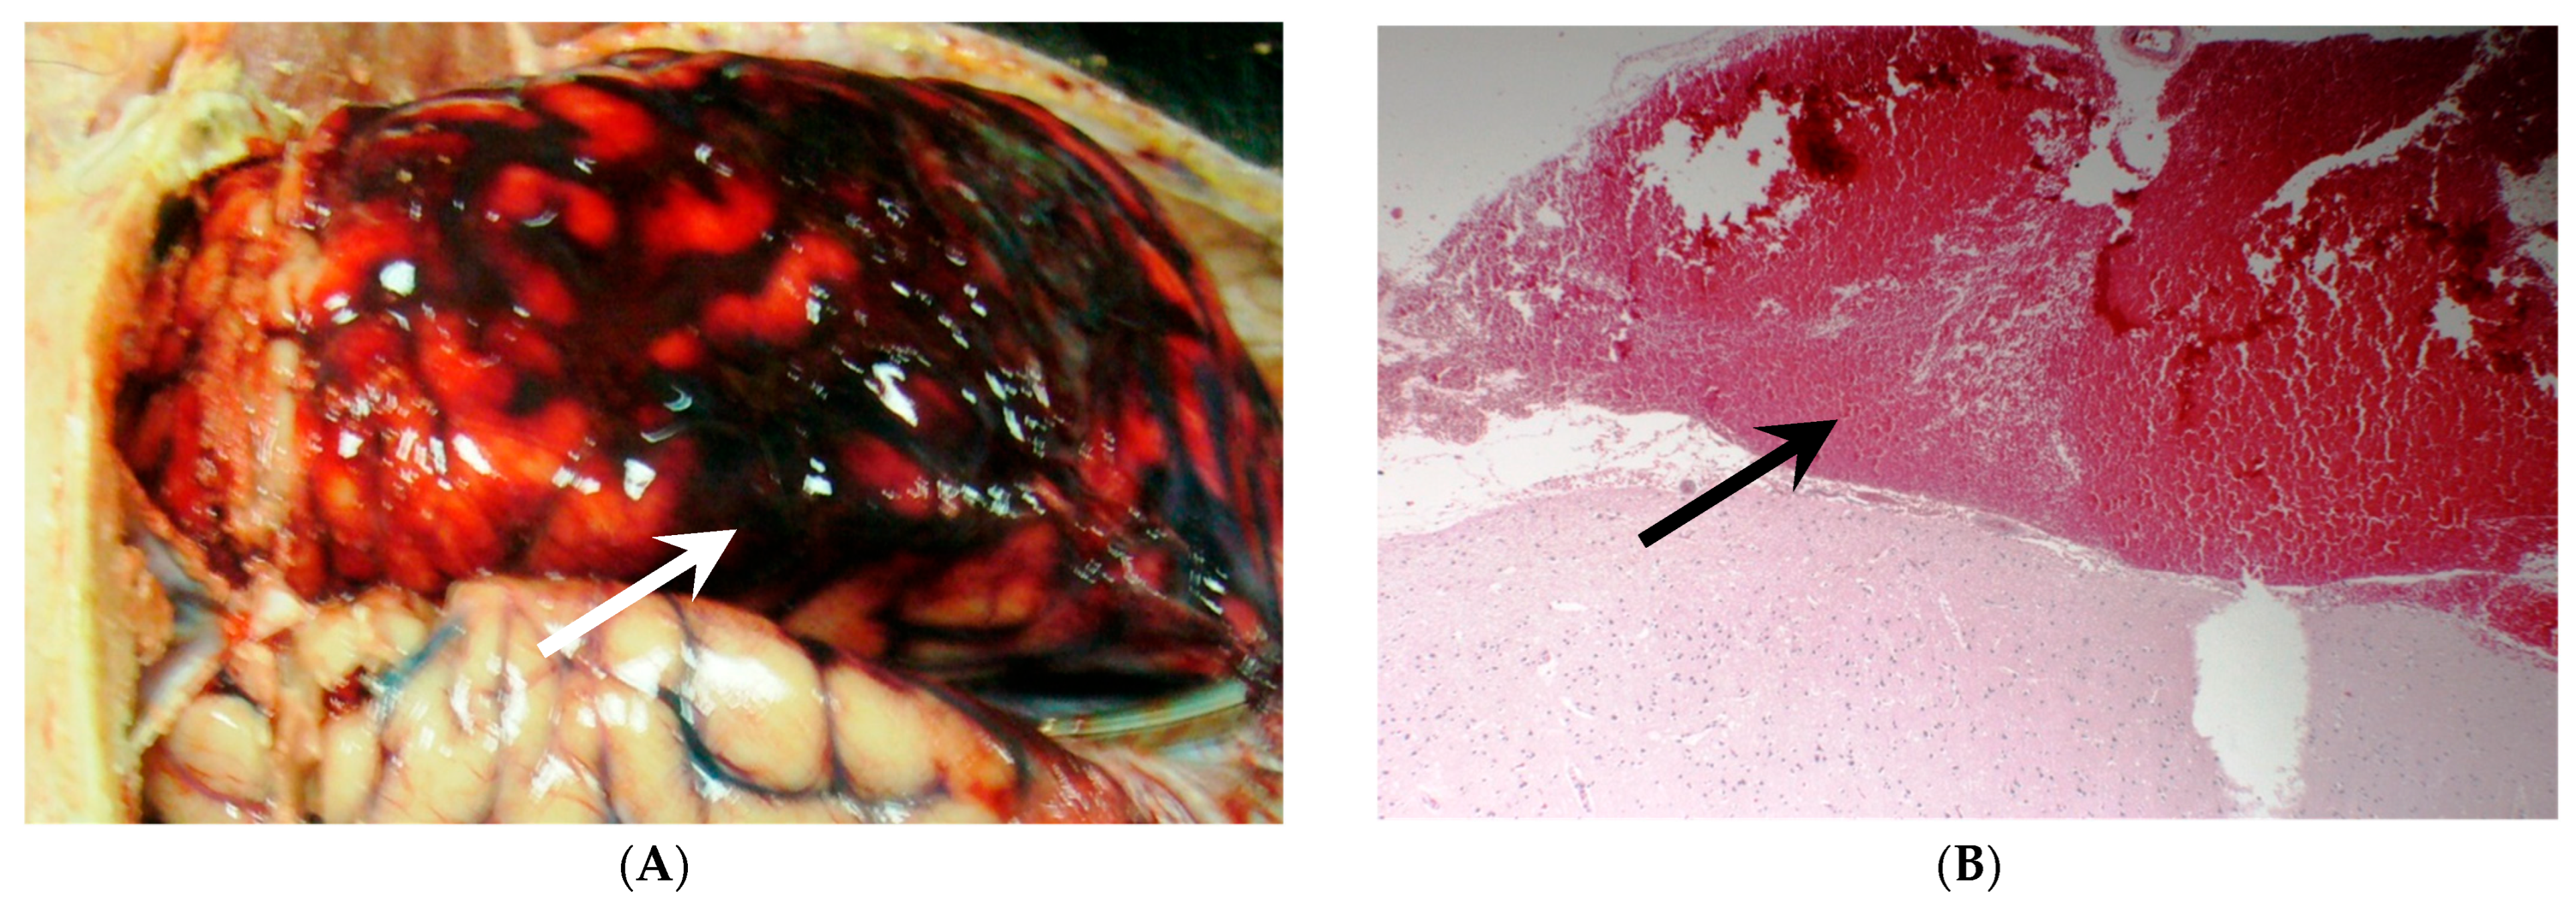

- Hayman, E.G.; Wessell, A.; Gerzanich, V.; Sheth, K.N.; Simard, J.M. Mechanisms of Global Cerebral Edema Formation in Aneurysmal Subarachnoid Hemorrhage. Neurocritical Care 2017, 26, 301–310. [Google Scholar] [CrossRef]

- Dreier, J.P.; Lemale, C.L.; Kola, V.; Friedman, A.; Schoknecht, K. Spreading depolarization is not an epiphenomenon but the principal mechanism of the cytotoxic edema in various gray matter structures of the brain during stroke. Neuropharmacology 2018, 134, 189–207. [Google Scholar] [CrossRef] [PubMed]